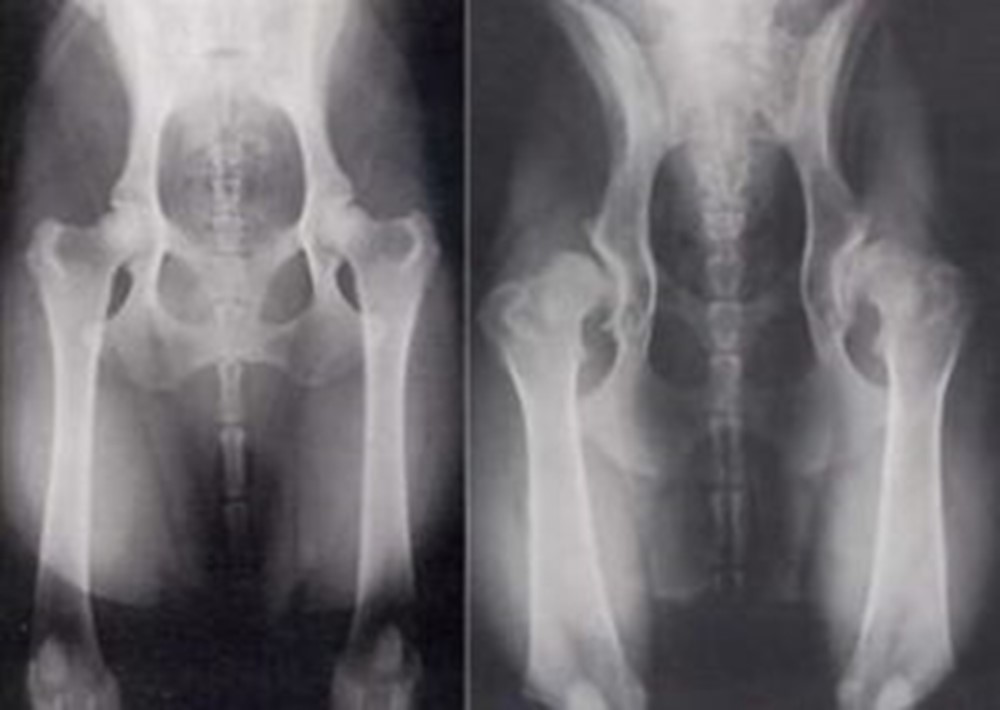

Kalça çıkığı tespit edilen çocuklarda hemen tedavi başlanmalıdır. tedavi; erken dönemde bandaj, cihaz veya alçıyla yapılırken ilerleyen ve gecikmiş hastalarda ameliyatla çözüm sağlanabilmektedir.